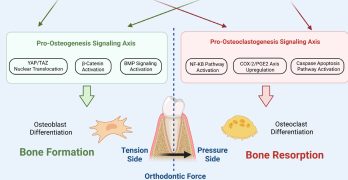

Mecanobiología en el movimiento Ortodontico: Actualizando Nuestra Comprensión para la Clínica

El movimiento ortodóncico (Orthodontic tooth movement - OTM) es un fenómeno biológico complejo, no solo mecánico. El … [Leer más...] acerca de Mecanobiología en el movimiento Ortodontico: Actualizando Nuestra Comprensión para la Clínica